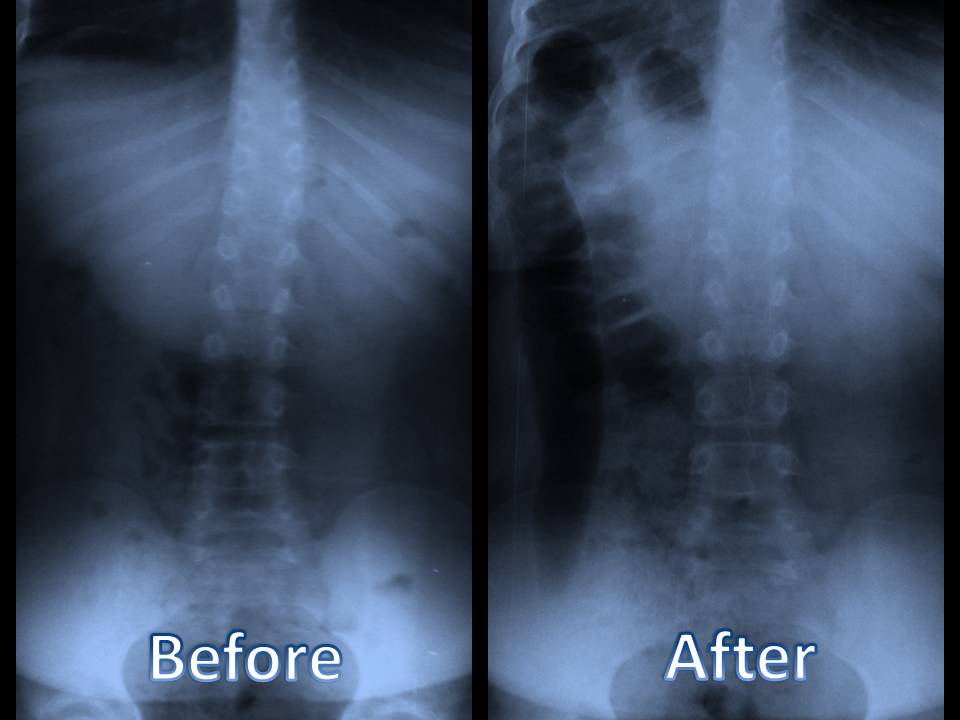

Your medical professional may also recommend a collection of imaging treatments to figure out the reason for your neck and back pain. These imaging treatments can include x-rays, bone scans, and also CT scans. These imaging treatments can be valuable, but they aren't always necessary for many cases of back pain. If you have extreme pain in the back, your physician might advise an injection. These shots can assist to relieve pain as well as lower inflammation.

3. Diagnosis of Back Pain